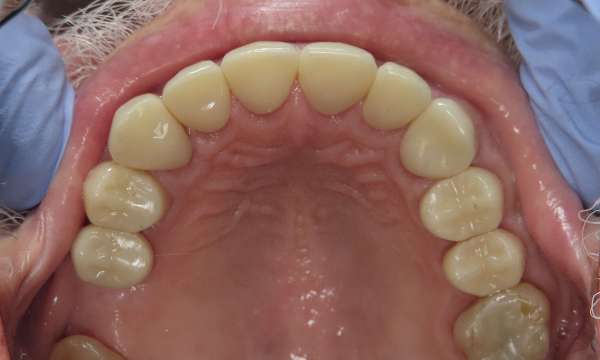

Full Mouth Restoration

This patient had severely worn most of his teeth from many years of clenching and destructive tooth grinding.  We were able to take him from his consultation, to a discussion of his options, to a final result of single crowns on most teeth with a bridge in the lower front.  We were so happy to deliver this result, improving his confidence, function, and quality of life.